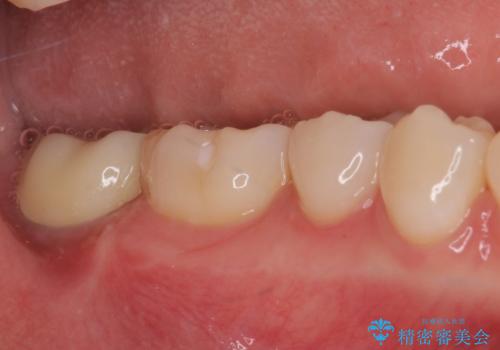

歯の高さが低く、かぶせものを安定して維持させることができないため、歯冠長延長術により歯の高さを増大させた上で、オールセラミッククラウンにて補綴することとしました。

歯の高さが増したことで、かぶせものが外れにくくなったことはもちろん、今まで無理と言われていたセラミッククラウンも装着でき、さらには歯間部の清掃性も向上したため、患者様には大変満足していただけました。